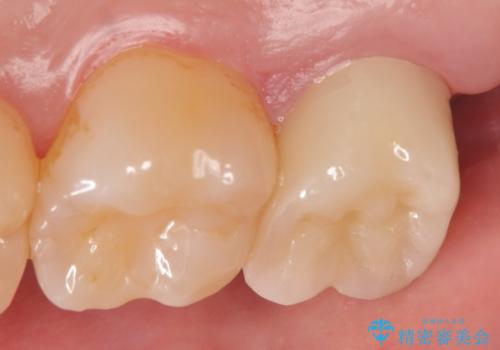

- 右上7の虫歯が大きく、他院にて抜歯と言われたが、なんとか残せないかと当院にいらっしゃった方の症例です。

自発痛の既往および持続痛を認めたため、カリエス除去後根管治療を行いました。

その後オールセラミッククラウンによる補綴を行いました。

今回用いたオールセラミッククラウンはジルコニアフレームという白い素材の上にセラミックを盛っているため、審美性が非常に高いのが特徴です。

また、ジルコニアは人工ダイヤモンドの材料にも使われているほど高い強度を持っており、そのためオールセラミッククラウンは審美性だけでなく、奥歯やブリッジの補綴も可能とするクラウンです。